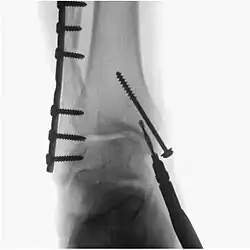

Surgical fluoroscopy

Fluoroscopy is used in various types of surgical procedure, such as orthopaedic surgery and podiatric surgery. In both of those, it is used to guide fracture reduction and in use in certain procedures that have extensive hardware. Specifically, once the fracture is realigned, a surgeon will (with the assistance of their surgical technologist) drill a guide pin into the bone tissue and use fluoroscopy to insure proper angle of the pin - then a cannulated drill bit is inserted over the pin to prepare a ‘hole’ for a bone screw. If the surgeon prefers a different angle, they simply reverse the pin and redrill. Fluoroscopy will be use for each screw placed -which has greatly improved proper fracture heal due to more accurate reduction.[5]